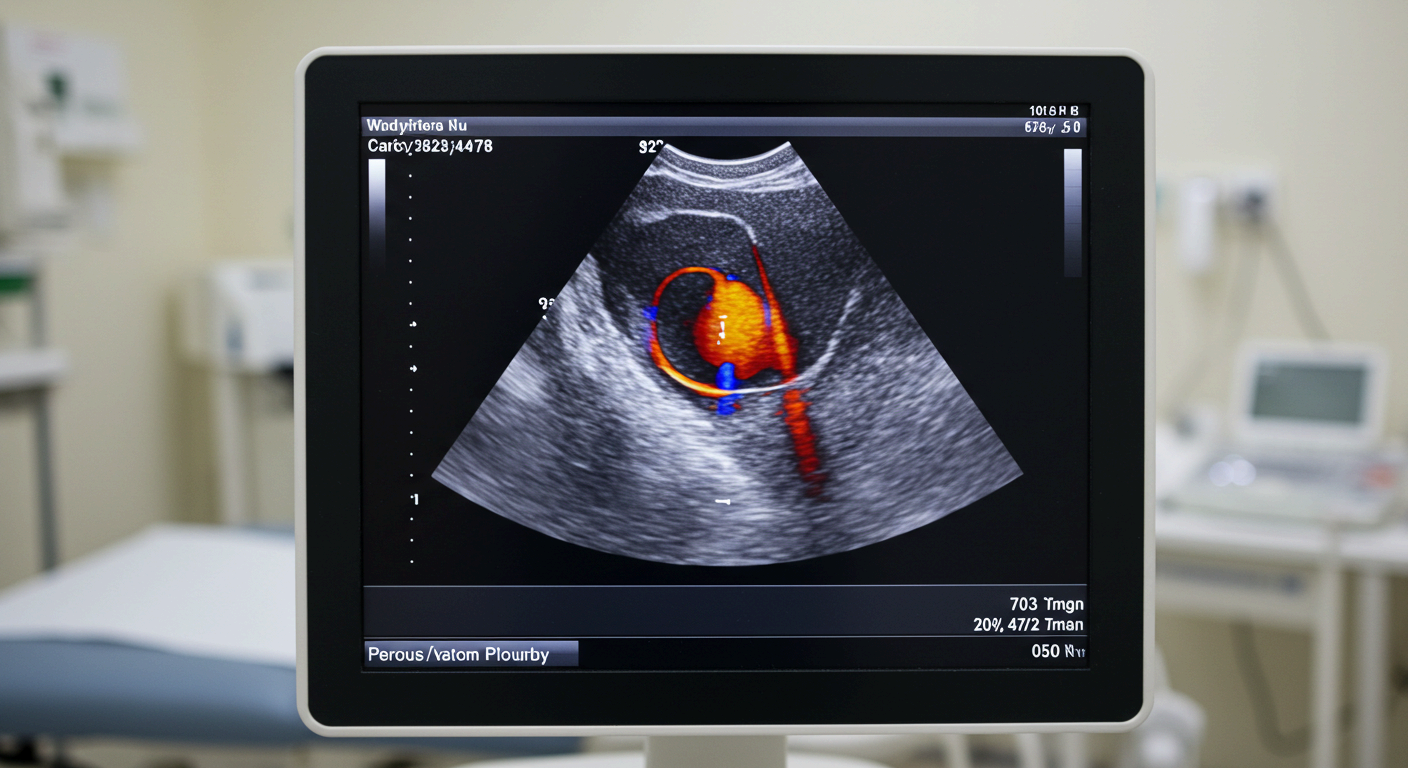

- 초음파 도플러 기능을 통해 협착 부위의 혈류 속도 증가 여부를 파악할 수 있으며, 협착 정도(30%, 50%, 70% 이상 등)를 수치로 명확하게 분석할 수 있습니다.

- 초음파를 통해 이중 벽 구조(Flap)를 포착하거나, 혈류 흐름 이상을 실시간 확인할 수 있습니다.

- 초음파는 혈류 속도 감소, 흐름의 왜곡 등을 통해 혈전 존재 가능성을 추정합니다.